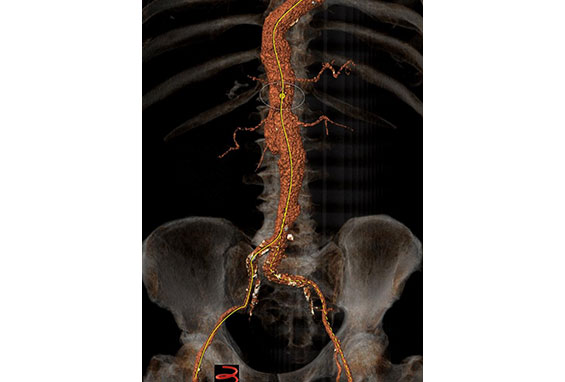

Περίπτωση 3

Άνδρας ασθενής 65 ετών με ανεύρυσμα κοιλιακής αορτής μέγιστης διαμέτρου 5,8 εκατοστών που αρχίζει αμέσως κάτω από τις νεφρικές αρτηρίες (παρανεφρικό), παχύσαρκος, με πολλαπλές συνοδές παθήσεις που αποκλείουν την ανοιχτή χειρουργική αποκατάσταση, η οποία με την σειρά της παρουσιάζει σημαντική πιθανότητα για μετεγχειρητικές επιπλοκές

Αντιμετωπίστηκε ενδαγγειακά με την τεχνική χρησιμοποίησης εξατομικευμένου μοσχεύματος τύπου Zenith με πλάγιες οπές (fenestrations), στις 2 νεφρικές αρτηρίες και την άνω μεσεντέριο αρτηρία με επιπρόσθετη ευρεία εγκοπή (scallop) για την κοιλιακή αρτηρία, το οποίο σχεδιάστηκε αποκλειστικά για την περίπτωση του